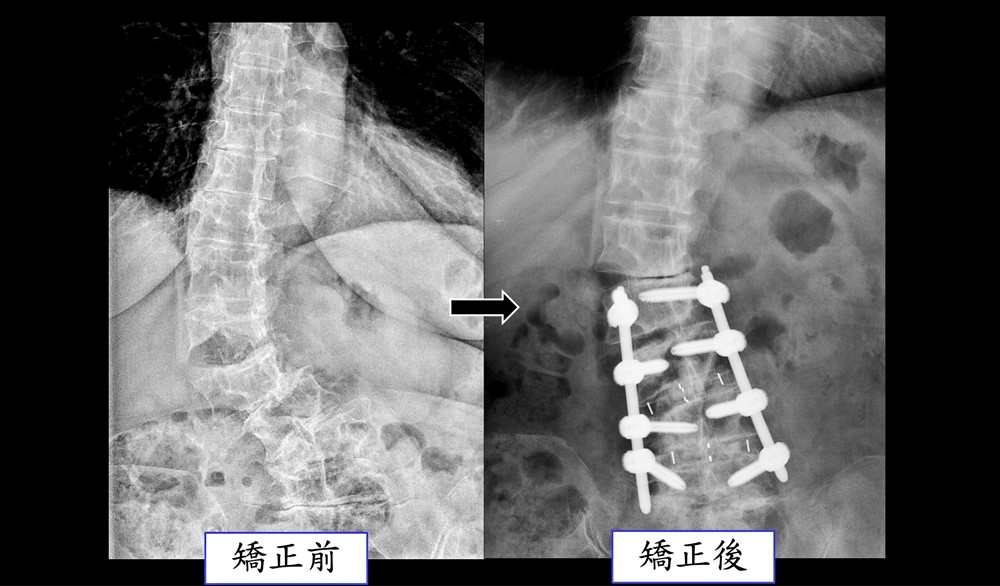

六十四歲女性於七年間側彎情況加劇、嚴重錯位。

接受手術治療後完全矯正。

另一位女性病人是六十四歲保母,初發現脊椎側彎時,角度還不嚴重。但因工作需要抱小孩和長時間站立,加上有扁平足和風濕免疫疾病,七年後,脊椎側彎角度已經惡化到整個脊椎骨都錯位。病人在多家醫院看診也都診斷需要手術,不過病人骨質不好,手術難度很高。最後,選擇了台中慈院微創脊椎關節中心。

張主任採用電腦導航前開加後開的手術,先從腹部矯正脊椎骨,再從背後固定支架。術後,病人脊椎側彎角度完全矯正回來,五天左右就出院。張主任指出,微創脊椎手術治療嚴重脊椎側彎具有多項優點,包括傷口小,破壞組織少,術後疼痛輕微,復原時間更短;有電腦導航輔助,精準矯正脊椎角度,減少手術風險;適用於骨質較差的病人。